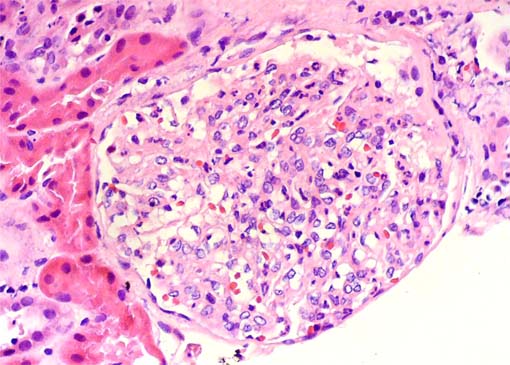

Figura 4.

H&E, X400.